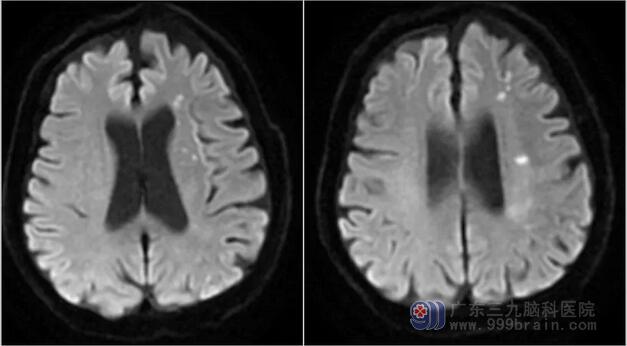

原来最初发病的时候,钟叔只是表现为双下肢麻木,走起路来好像踏在棉花上一样,随即钟叔就到当地医院就诊。当地医院完善头颅核磁后发现右侧基底节、左侧放射冠区、左侧半卵圆中心脑梗死;而磁共振血管成像则发现左侧颈内动脉重度狭窄。

外院核磁影像